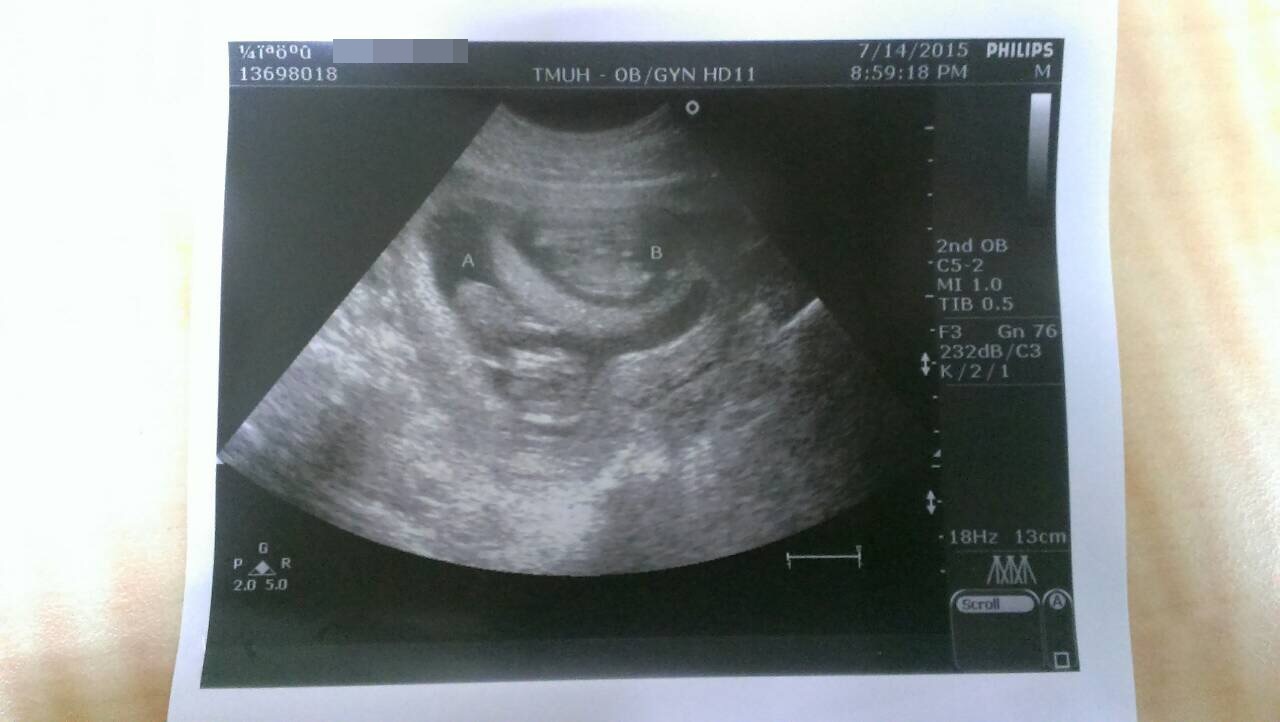

這次的招音波,超音波師一樣細心的測量寶寶的心跳、身長

目前A寶、B寶來到了4.69 &4.46 cm

有趣的是~

B寶看似乖乖橫躺(頭在右邊,身體在左邊),但過程非常活潑一直動來動去

而A寶,竟然呈現一個『倒頭栽』的睡姿,

頭下腳上,臉還整著埋起來 (這根本就老公在家的趴睡姿勢阿!)

叫了老半天,才稍微給我不情願的翻身背對,實在是很搞笑